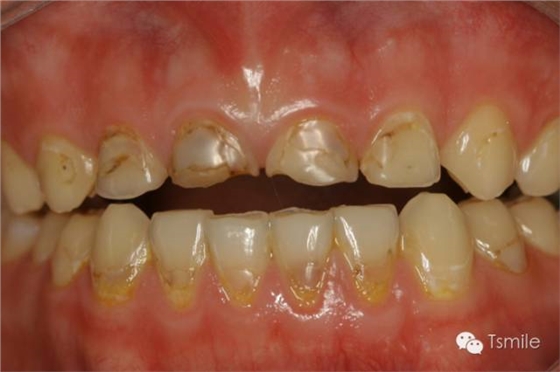

牙列重度磨耗的病因--化學(xué)因素 化學(xué)因素 牙列重度磨耗的化學(xué)因素病因是指酸性物質(zhì)對(duì)牙齒硬組織(牙釉質(zhì)和牙本質(zhì))中的羥基磷灰石的酸蝕脫礦而導(dǎo)致的牙齒表面硬組織的缺損,又稱(chēng)酸蝕癥(erosion)。酸蝕癥根據(jù)對(duì)牙齒酸蝕脫礦的酸的來(lái)源可分為外源性酸蝕和內(nèi)源性酸蝕。 (1)外源性酸蝕 對(duì)牙齒酸蝕脫礦的酸來(lái)源于患者身體以外,包括飲料、食物、水果、藥物、工作環(huán)境等。碳酸類(lèi)飲料如可樂(lè),其PH值約為2.7;果汁中檸檬汁的PH值約為1.8-2.4。酸性的飲料、水果、食物等長(zhǎng)時(shí)間、高頻度地接觸牙齒表面,導(dǎo)致牙齒表面硬組織酸蝕脫礦,造成牙齒表面硬組織的重度缺損。

圖3:酸性飲料導(dǎo)致的牙列重度磨耗(酸蝕癥)